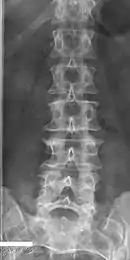

Block vertebrae of the cervical spine (vertebrae 4 and 5). Probably based on degenerative or inflammatory changes.